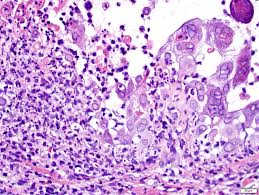

Histopathological features and serological testing were consistent with herpetic esophagitis. All three of the following are required for the diagnosis of gerd; There is apparently a word for heartburn in sumerian. Herpes simplex, varicella and herpes zoster infections show identical histology.clinical correlation or immunohistochemistry and/or viral culture or pcr (of an appropriate swab or tissue specimen) is required to differentiate these viral infections. Cytomegalovirus (cmv) esophagitis is treated differently from hiv esophagitis. He had no history of recurrent infections or history of sick contacts. Esophagitis caused by herpes simplex virus (hsv) is frequently documented during periods of immunosuppression in patients infected with human immunodeficiency virus (hiv). Cutaneous bullous disorders should be ruled out immunofluorescence is negative for c3 and ig

Esophagitis caused by herpes simplex virus (hsv) is frequently documented during periods of immunosuppression in patients infected with human immunodeficiency virus (hiv). Lymphocytic esophagitis is characterized by high numbers of intraepithelial lymphocytes (iels) gathered mainly around peripapillary fields and by none (n = 12) to occasional (n = 8) cd15+ intraepithelial granulocytes. The histology of herpes infections is very distinctive. The acute inflammation can be caused by infections, ingestion of irritative chemicals, drugs such as nsaids, chemotherapy, and radiation. His immunological work up showed normal level of immunoglobulins and his white blood cells subpopulations were normal. We reviewed 16 cases of hsv esophagitis diagnosed from january 1982 to march 2016. The low power pattern of a typical lesion. Hsv esophagitis is usually identified in patients with aids or other significant immunosuppressive conditions, although cases in healthy adults also occur.

His immunological work up showed normal level of immunoglobulins and his white blood cells subpopulations were normal. As an immunopathology analytical specialist in molecular pathology, jim's primary job functions included daily ihc quality control and managing the daily technical aspect of the clinical immunopathology operation. In a child with esophagoscopy showing erythema with or without ulceration and esophageal biopsy revealing inflammation, hsv etiology was established based on the presence of one or more of the following criteria: The histology of herpes infections is very distinctive. Hsv esophagitis is usually identified in patients with aids or other significant immunosuppressive conditions, although cases in healthy adults also occur. Original posting / last update: The differential diagnosis in a patient with a swallowing disorder or other problem with food intake includes both local and systemic problems. #2 most common cause of infectious esophagitis after candida self limited in healthy patients; Clinical characteristics and endoscopic features were retrospectively reviewed and categorized. Esophagitis caused by herpes simplex virus (hsv) is frequently documented during periods of immunosuppression in patients infected with human immunodeficiency virus (hiv). The esophagus is a muscular tube that carries food and drink from your mouth to your stomach. He had no history of recurrent infections or history of sick contacts. Graman, in mandell, douglas, and bennett's principles and practice of infectious diseases (eighth edition), 2015 herpes simplex virus esophagitis.